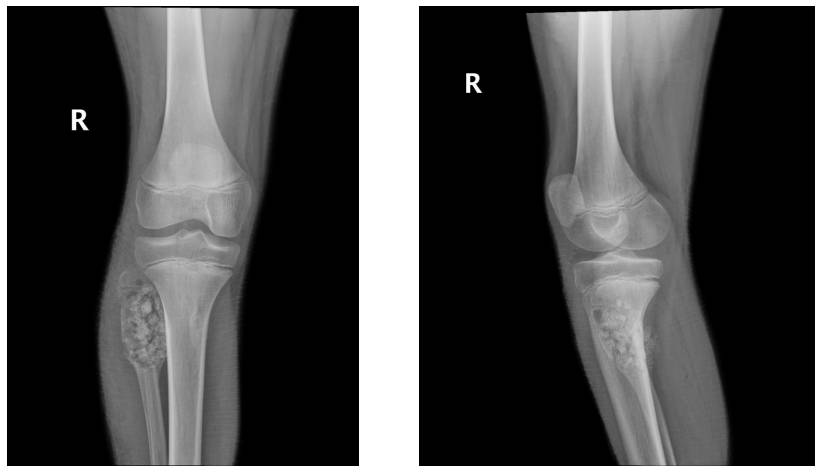

VAKA 15: Diz (Proksimal Fibula) Yerleşimli Anevizmal Kemik Kisti

Diz bölgesinde şişlik ve ağrı şikayeti ile tarafımıza başvuran, iğne biyopsisi ile anevrizmal kemik kisti tanısı konulup agresif küretaj sonrası küretaj yapılan erkek çocuğu hastamız.

Ameliyat Öncesi: Röntgende proksimal fibulada harabiyete ve ekspansiyona neden olan litik lezyon görülmekte